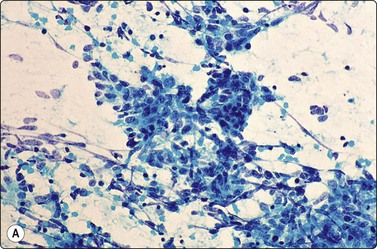

image

Fig. 8.1 Bronchiolar epithelium

Small sheet of regular glandular cells (Pap, HP).

Fig. 8.2 Mesothelial cells

Monolayered sheet of cells showing ‘spongiotic’ separation of individual cells within the sheet (Pap, LP).

Fig. 8.3 Alveolar macrophages

Loose aggregates and dispersed cells with rounded nuclei, small nucleoli, and abundant finely vacuolated cytoplasm (Pap, HP).

Bronchial epithelium may be abundant in percutaneous FNB if the needle traverses a medium-sized bronchus or tracks along a bronchial lumen. Transbronchial FNB may also yield abundant bronchial epithelium. Bronchial epithelium appears as small palisaded clusters with a ciliated border. In large aggregates the cells may present as flat sheets with a pavement-like aspect, but ciliated cells can usually be observed at the edges of these sheets.

Bronchiolar epithelium or nonciliated epithelium is seen commonly as sheets of various size (Fig. 8.1). They usually have irregular edges and the component cells display variable cell separation. The nuclei are generally small and there is a low nuclear:cytoplasmic (N:C) ratio. Sometimes the nuclear outlines are slightly irregular and small intranuclear cytoplasmic inclusions are observed. Occasionally, atypia of bronchiolar epithelium may be quite pronounced, for example in reactive or inflammatory processes; however, the number of atypical cells is usually small. A diagnosis of malignancy should generally not be made on the basis of small numbers of cells.

Page 215

Mesothelium can be easily distinguished from bronchiolar epithelium. It is seen as various-sized, flat, monolayered sheets; there is usually more cell separation than in bronchiolar epithelium, which sometimes gives a sponge-like appearance. The cells appear to be joined by intercellular bridges similar to those of squamous epithelium in histological sections. (Fig. 8.2). Reactive mesothelium can appear atypical and be misinterpreted as neoplastic.

Normal lung yields a population of macrophages widely dispersed over the slide (Fig. 8.3); these contain small particles of brown or black particulate matter, some of which is inhaled dust, especially in smokers. Many hemosiderin-laden macrophages usually imply tissue or blood breakdown near the lesion and may add to a suspicion of pulmonary infarction should the clinical background be appropriate.